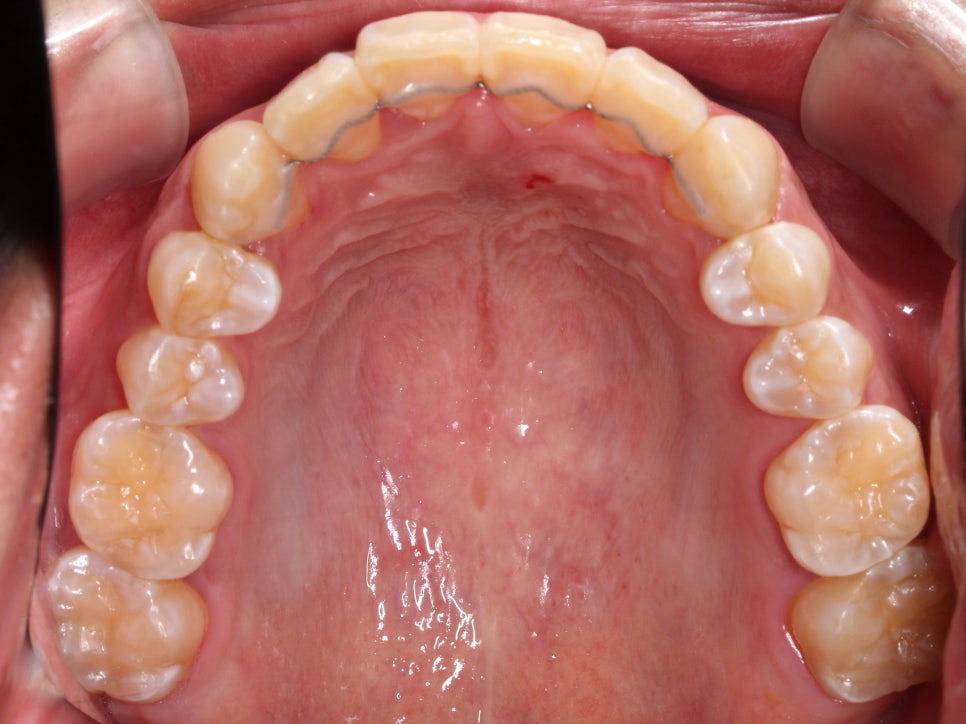

첫 방문 때 이렇게 아래 앞니도 깨져있고,

#12 치아는 안으로 들어가 있었습니다.

환자분은 #13 이 튀어나왔다고 생각하시던데,

이렇게 씹는 면 사진으로 보면

#13이 튀어나왔다라기보단

#12가 상대적으로 들어가 있는 게 맞죠.

치주치료도 필요하신 분이고,

충치치료도 필요한 부분들이 보였습니다.